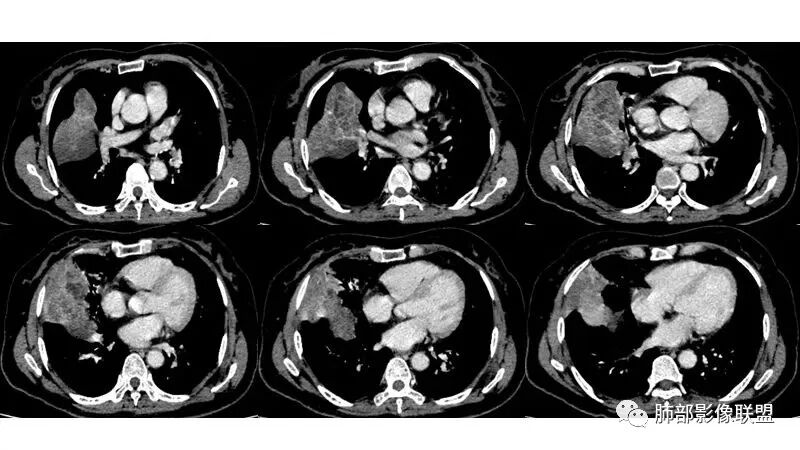

这个病例,看长轴、形态,首先跨叶,里面的坏死腔,它是相通的,就是跨中叶及前基底段。

看中叶外侧段的病变,我观察到支气管与坏死腔相通的,支气管这种堵塞就不踏实了,假如是腔内的病变,就不太支持。

如果是腔内的病变,第一,应该是局限在某个叶的,不可能上下叶都有。所以不太支持腔内的病变。因此考虑腔外的病变。腔外局限的肿瘤肯定不符合,假如这个病灶是个局限大肿块的话,里面肺动脉走势还可以。

然后中叶与下叶的坏死腔病灶是相通的,病灶是跨叶的,胸膜糊墙为主。

我要看一下下叶。还想重建一下,就是按照我自己理解的长轴去重建出这个病灶的整体形态,我当时一看,好像侧向融合的病灶。侧向融合的病灶考虑慢性炎性病变的,有几种,这样大片的病灶,常规都考虑特殊感染多一些,比如隐球,放线菌,奴卡等,都可以这样的改变。

现有的CT,里面存在坏死腔。炎症肯定有,是否同时合并肿瘤的问题?我需要详细的图将内部结构逐步剖析出来,看看能否有新的依据

南边:跨叶、楔形/边缘平直、支气管壁无破坏/连续/局部无膨大、实变区肺动脉走形自然、实性部分均匀、延迟强化、坏死腔内壁光滑/内壁强化环/近端与支气管相通,这些点均支持炎性。所以综合分析:符合炎性。